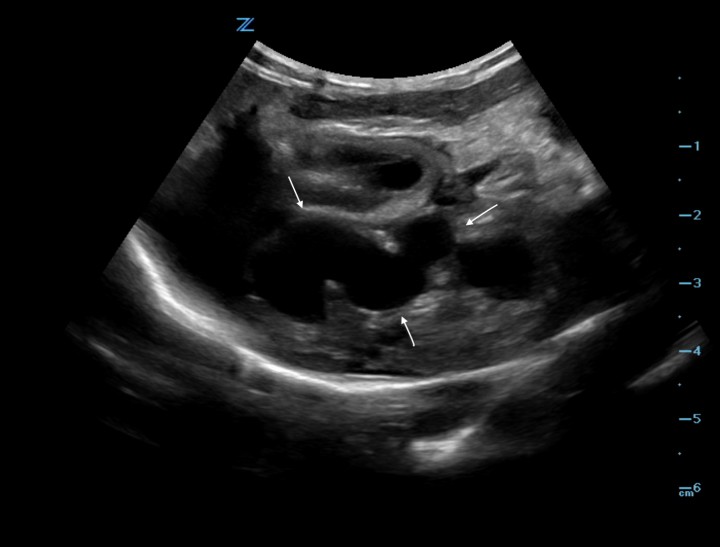

<p>Imagen ecográfica en un corte transversal donde se observa una estructura tubular anecoica en el lóbulo izquierdo hepático en relación con la vena porta intrahepática (flechas).</p>

Imagen ecográfica en un corte transversal donde se observa una estructura tubular anecoica en el lóbulo izquierdo hepático en relación con la vena porta intrahepática (flechas).